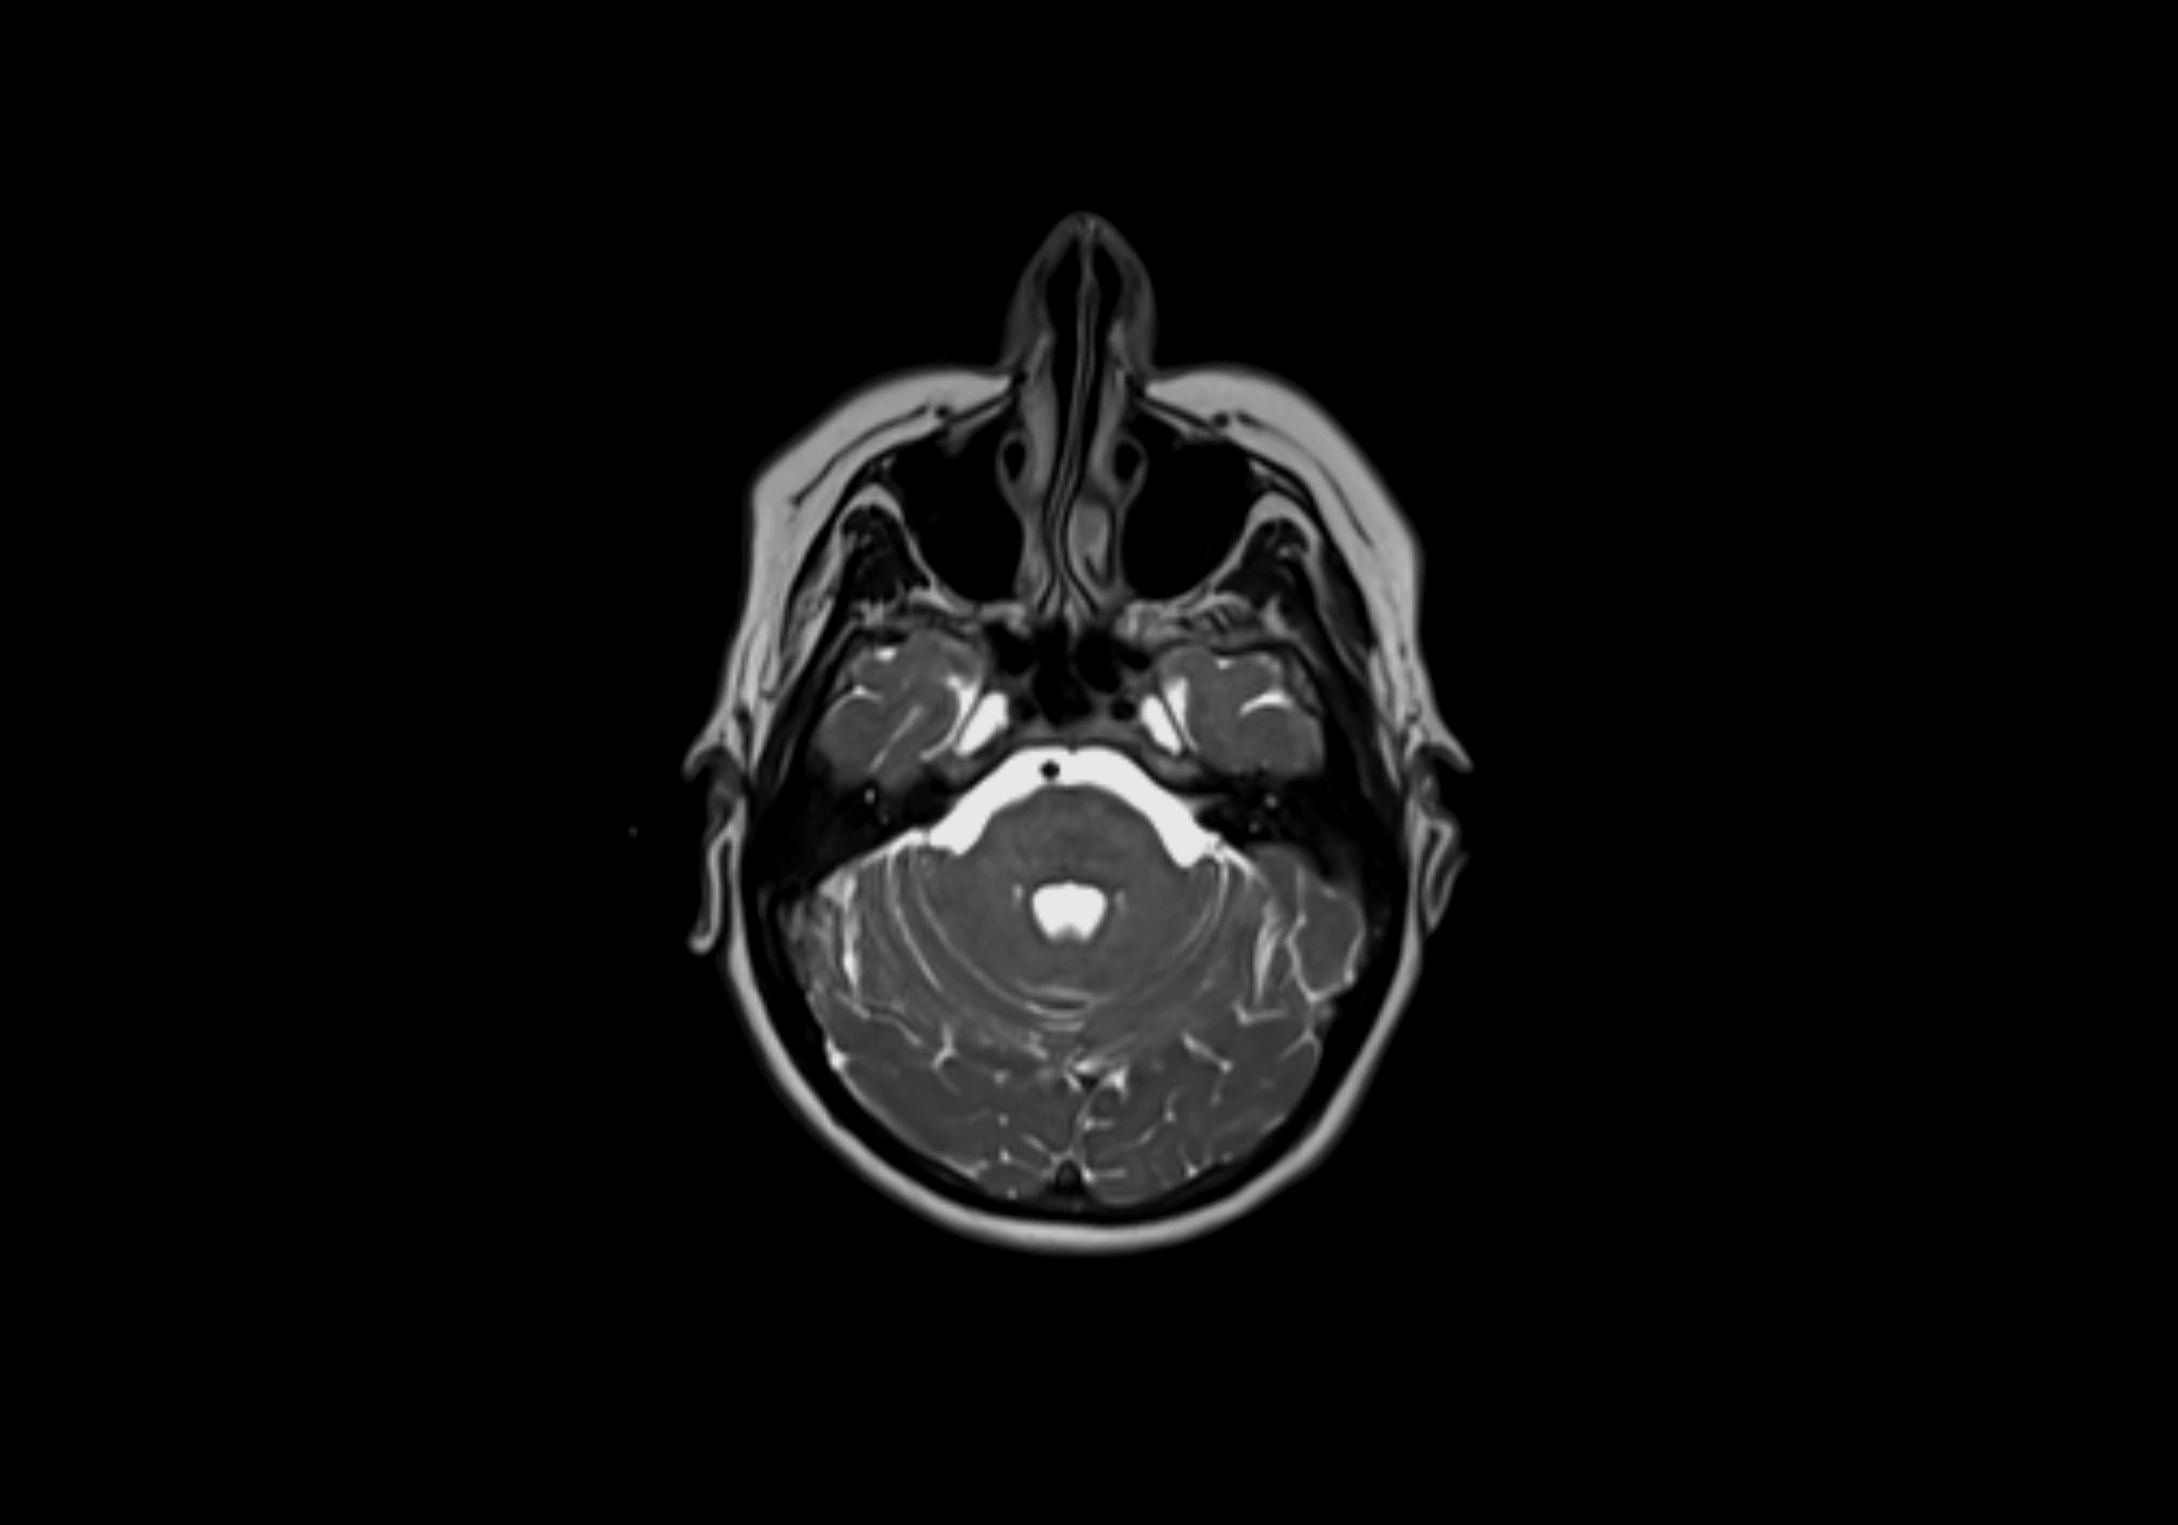

MRI Appearance

T2-weighted images:

• Nodes show intermediate signal, with surrounding fat bright

• Useful for detecting edema, inflammation, or infiltration

• Fatty hilum may appear slightly hyperintense relative to cortex

MRI images